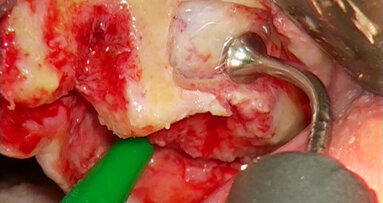

Stále častěji jsou na naši kliniku doporučováni pacienti, u nichž došlo k trvalé ztrátě citlivosti oblasti dolního rtu a brady nebo naopak neuralgiformním bolestem nervus alveolaris inferior v důsledku jeho poranění při implantaci nebo chirurgické extrakci retinovaného zubu. V těchto případech provádíme deliberaci tohoto nervu buď z přístupu ze sagitální osteotomie mandibuly nebo pomocí piezochirurgie. Následně odstraníme amputační neurom a nerv mikrochirurgicky rekonstruujeme (obr. 5a, 5b).